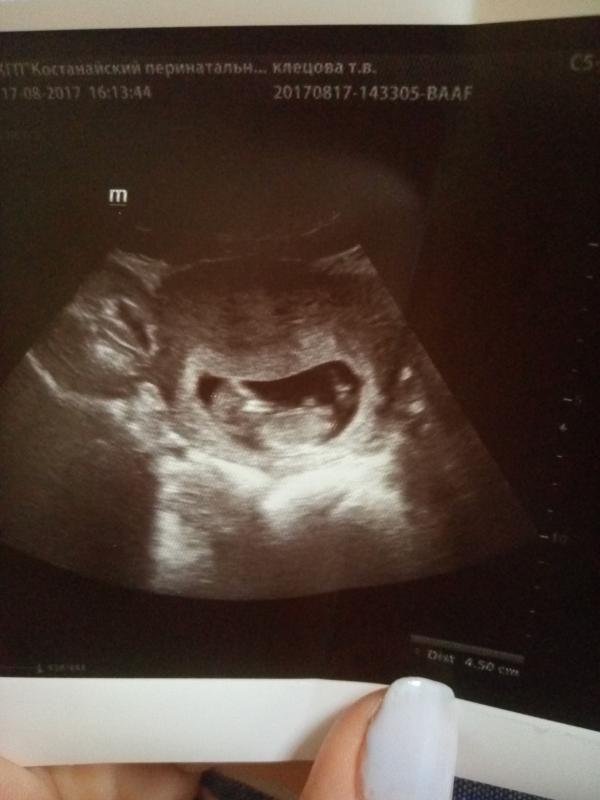

@little_fairy @mahalina93 сегодня с мужем смотрели и это такие эмоции как ножками, ручками двигает,переворачивается у мужа чуть слезы было видно😍😍😍😍

@little_fairy нет не скрининг, с консультации отправили сделать узи, а наша крошка еще маленькая для скрининга, всего 3мм не хватает, сказали прийти через 10 дней 😊